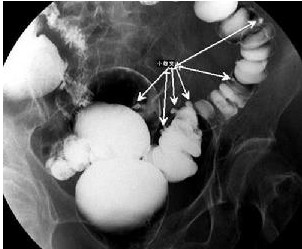

憩室炎的诊断,除了临床症状、体征之外,常需要结核必要的特殊检查。首先是确定憩室的存在,主要依靠消化道钡餐造影或钡剂灌肠,上消化道应首选前者而结肠则首选后者。其阳性率明显高于胃肠镜。但在鉴别憩室与结肠癌、溃疡性结肠炎、克隆恩病、阿米巴肠病、放射性肠炎等疾病时,肠镜检查仍有重要价值。然而,急性憩室炎时肠镜检查时禁忌症,因为可能引起肠穿孔。消化道出血是否由憩室炎所致,诊断书困难较大,可能需要做选择性动脉造影或胶囊胃镜。